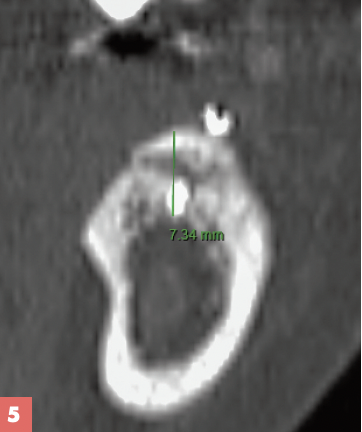

Après 4 mois et demi de cicatrisation osseuse, le bon volume osseux permet la pose de 2 implants Zimmer TSV de longueur 11,5 mm et 10 mm est réalisée (Fig. 5 à 7).

Le coffrage 3D « technique Khoury » permet un gain moyen de 7,2 mm. C’est la technique de choix pour la reconstruction des grands défauts transversaux et verticaux. Le prélèvement ramique permet d’obtenir un greffon autogène en qualité et quantité suffisantes, il peut être réalisé au piezotome ou à la microSaw (Dentply Sirona) qui montre aussi d’excellents résultats . Les suites opératoires du prélèvement ramique sont simples. Les contre-indications du coffrage rejoignent celles de l’implantologie. L’os allogénique peut être une alternative fiable néanmoins des auteurs rapportent un taux de complications plus élevé.